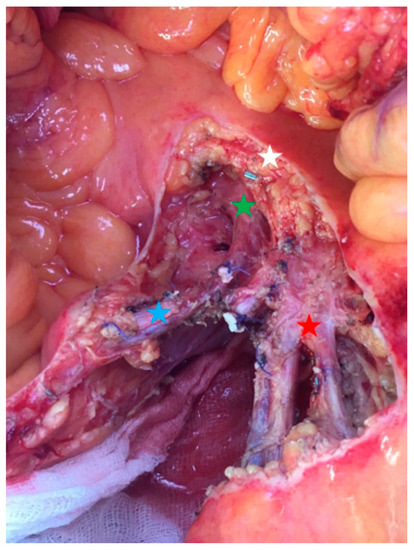

Figure 5.

Operative view focusing on the proximal nodal resection (group 3). Red star: proximal jejunal arteries and veins; blue star: superior right colic artery and vein; green star: superior mesenteric vein; white star: pancreas.